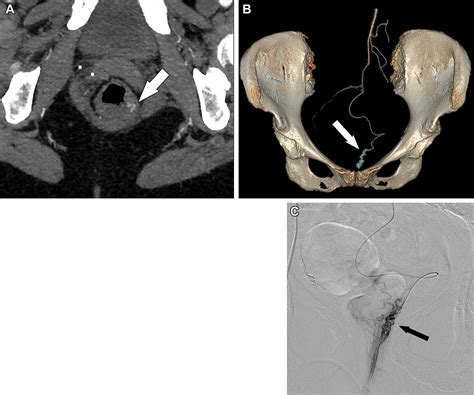

Because it is a minimally invasive technique, it does not require general anesthesia or incisions in the sensitive anal region. Instead, a tiny catheter is guided through a blood vessel in the wrist or groin to the specific arteries supplying the hemorrhoids. Small particles are then injected to block these vessels, successfully reducing the pressure and engorgement of the hemorrhoidal tissues.

2. Guidance: Using real-time X-ray imaging (fluoroscopy), the radiologist navigates a microcatheter through the vascular system.

3. Embolization: Once the specific hemorrhoidal arteries are identified, specialized embolic agents are injected to reduce the blood supply.